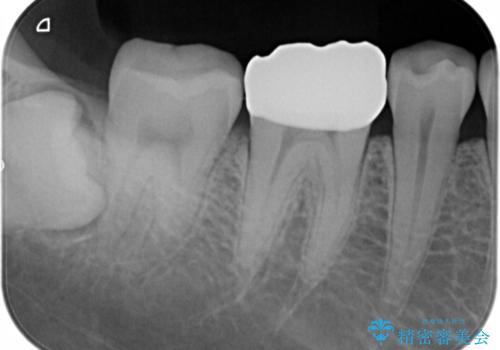

適合不良の補綴物は二次的な虫歯発生のリスクが高まります。

自費診療で用いられる材料は保険適応の材料に比べて、より精密で適合の良い被せ物作ることができるため、長期的な虫歯のリスクを大幅に減らすことが可能です。